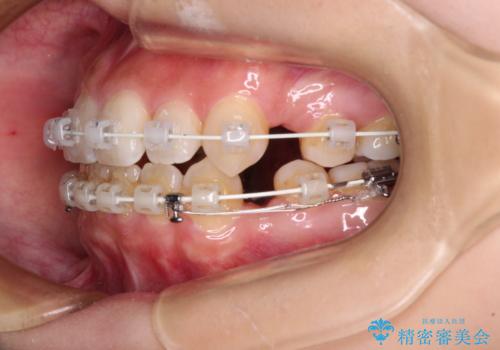

デコボコと八重歯の目立つ前歯 ワイヤー装置による抜歯矯正

- 審美装置

- 上下前歯のデコボコと八重歯を気にして来院された患者様です。

叢生を解消する際に出っ歯とならないようにするために、上下左右の小臼歯計4本を抜歯することとしました。

奥歯の咬み合わせが理想的であり、歯の移動に時間のかかる出っ歯でもなかったため、2年程度で治療を終えることを目標としましたが、無事に予定通りの2年間で終えることができました。